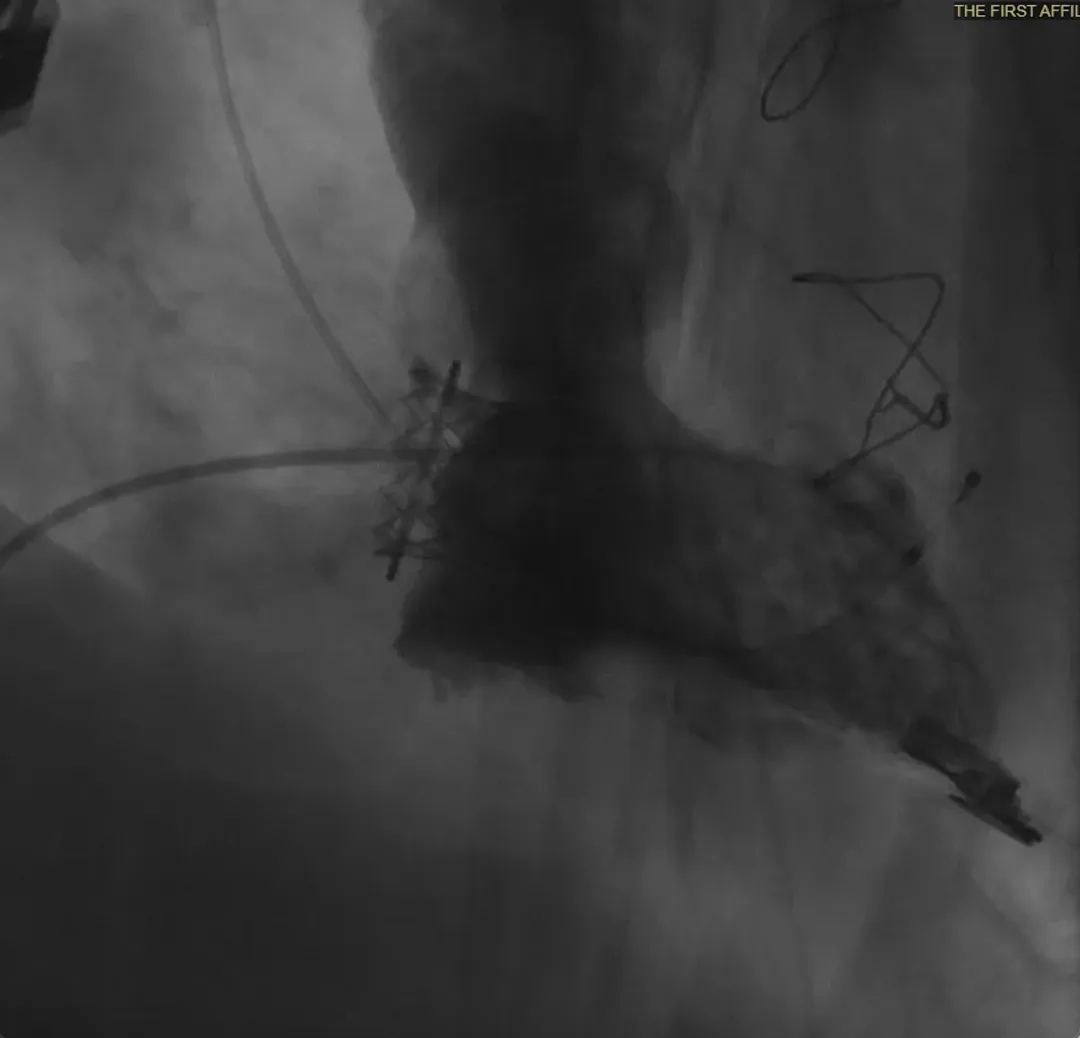

手术过程很顺利完成,新植入的瓣膜工作良好,且无任何反流情况出现。术后第二天,患者就顺利下床行走,随后顺利出院。

▲术中造影,提示瓣膜形态良好,未见瓣膜反流